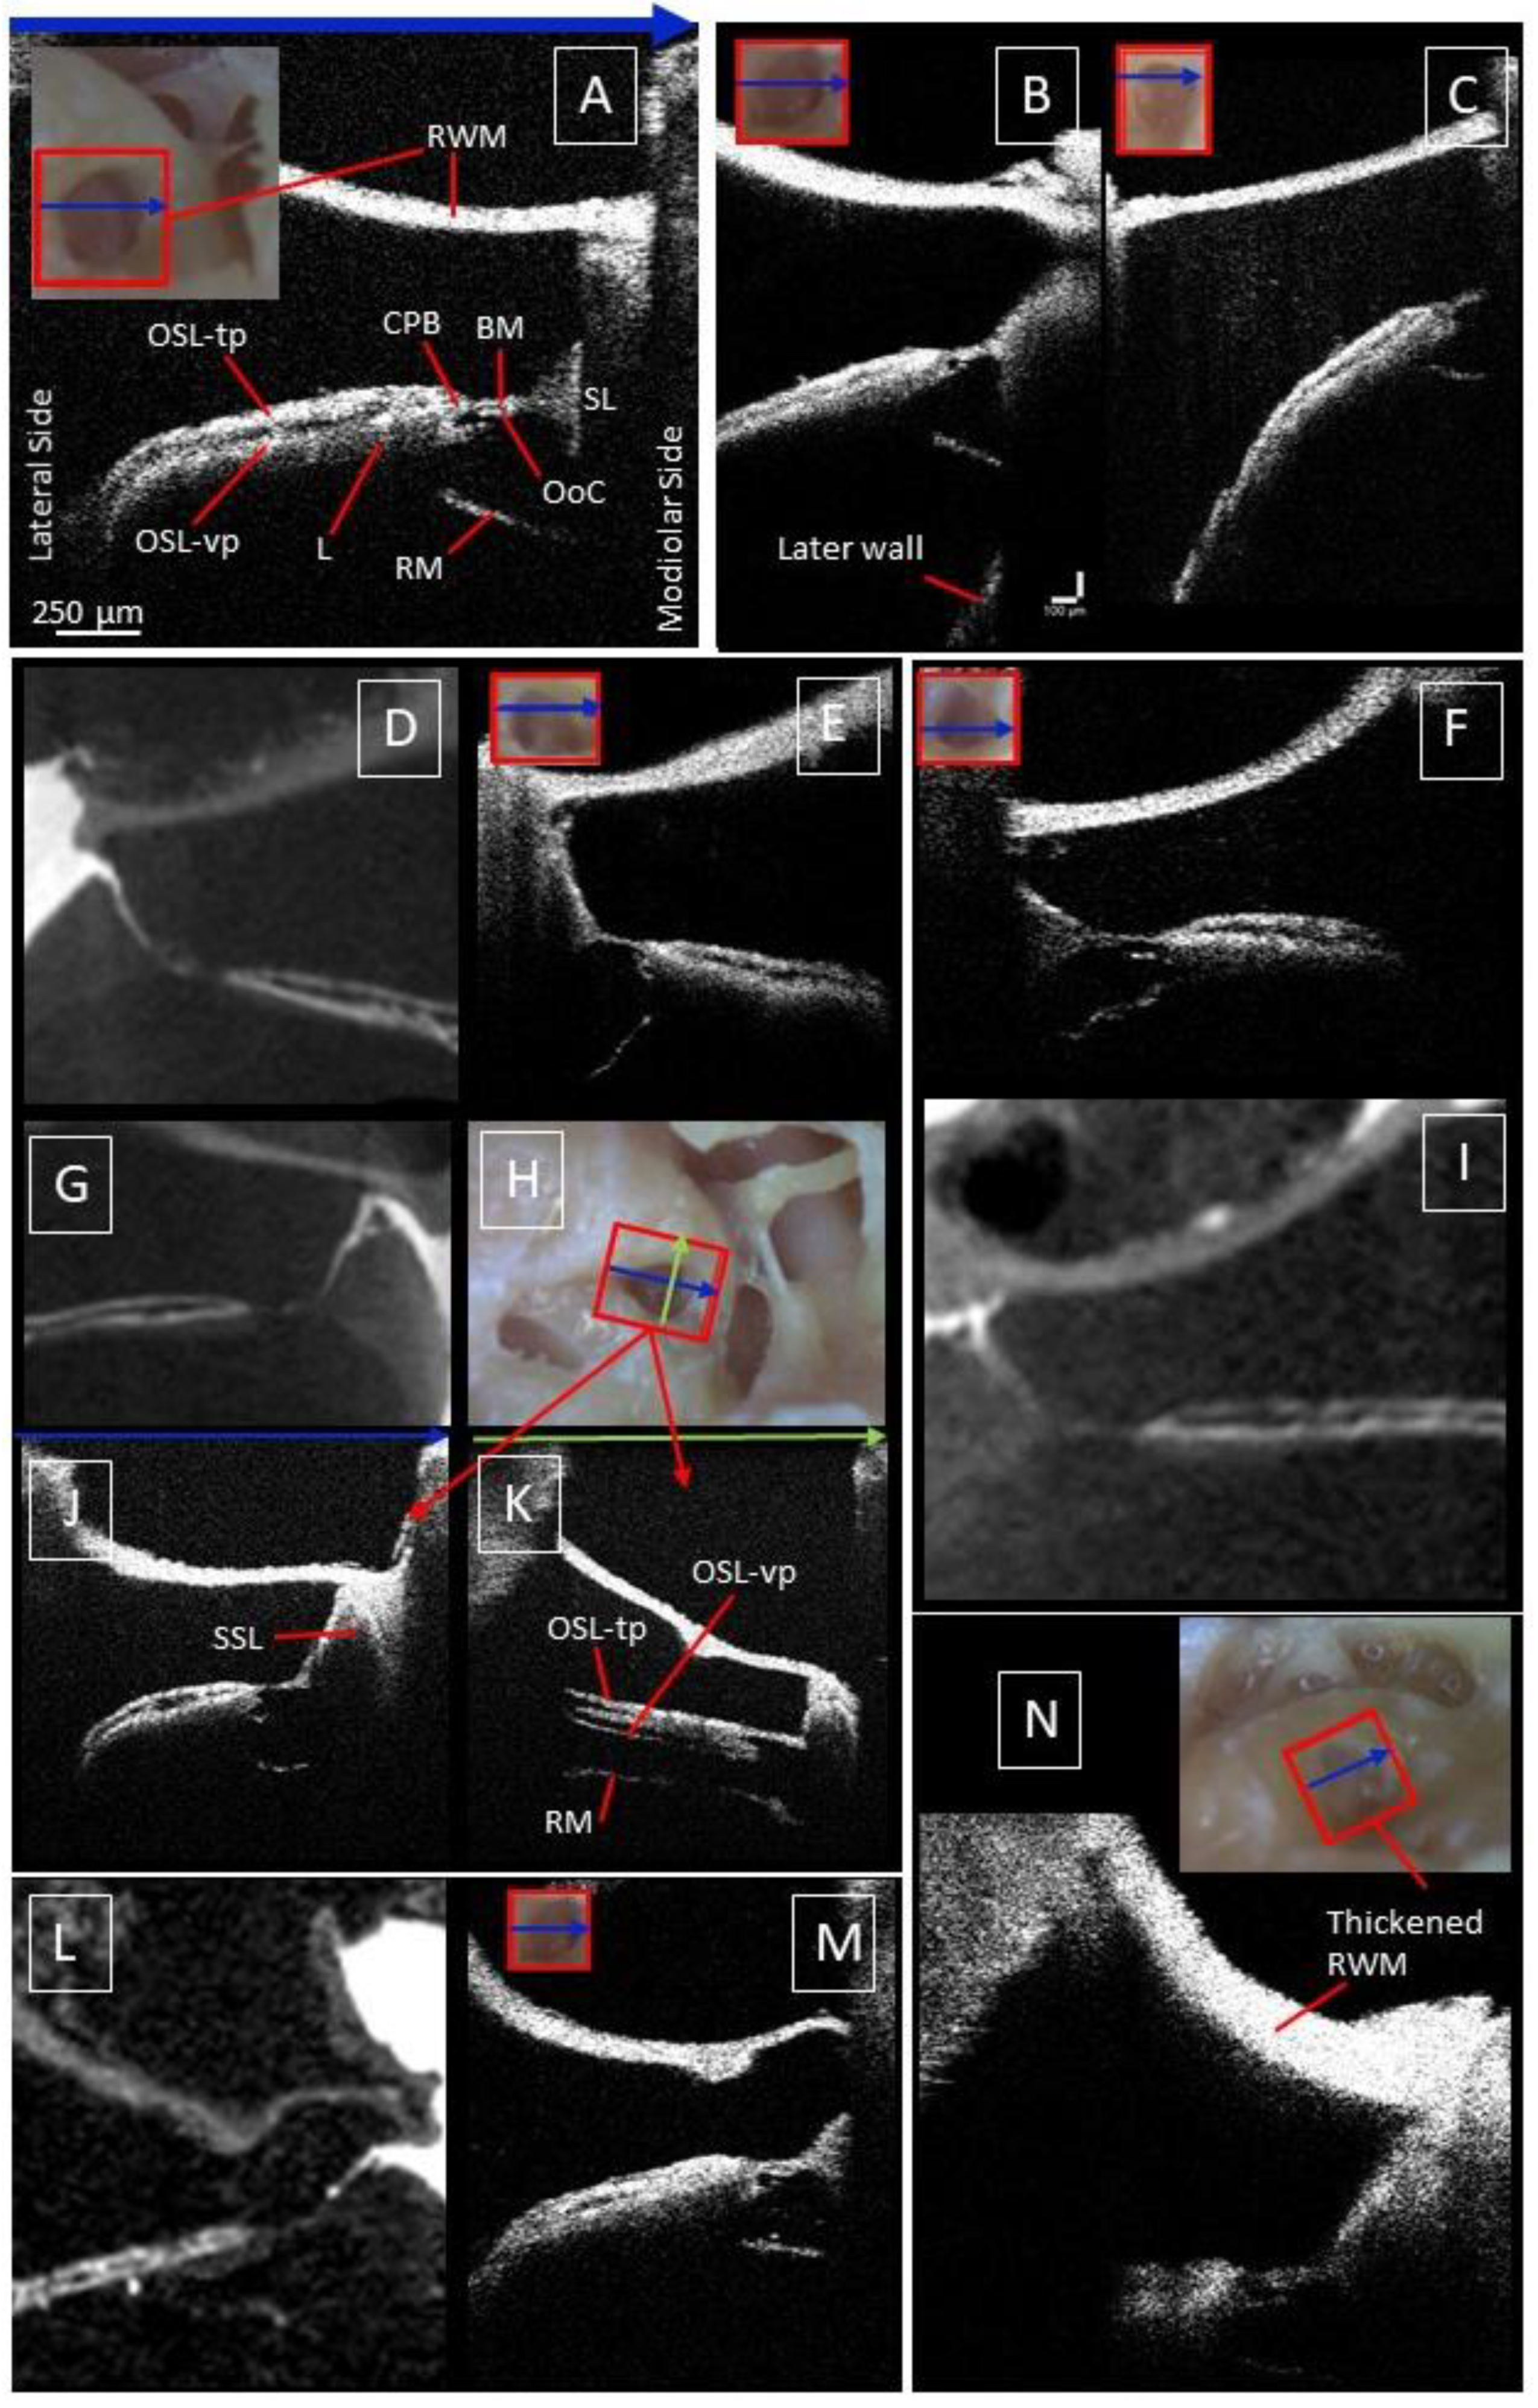

3.1. Intracochlear Microanatomy

3.2. The Human Organ of Corti

3.3. The Cochlear Partition Bridge and Spiral Limbus

3.4. Deviating Appearance of Intracochlear Structures

3.5. Factors Limiting Imaging through the RWM